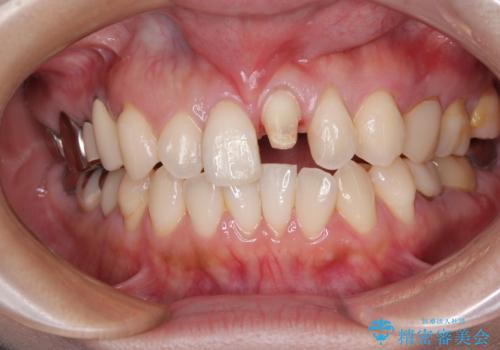

- 以前保険診療で行った前歯を自然できれいなセラミックにしたいと来院された患者様です。

古い材料と虫歯を除去して、土台の形を整え、より自然なオールセラミッククラウンにすることとしました。